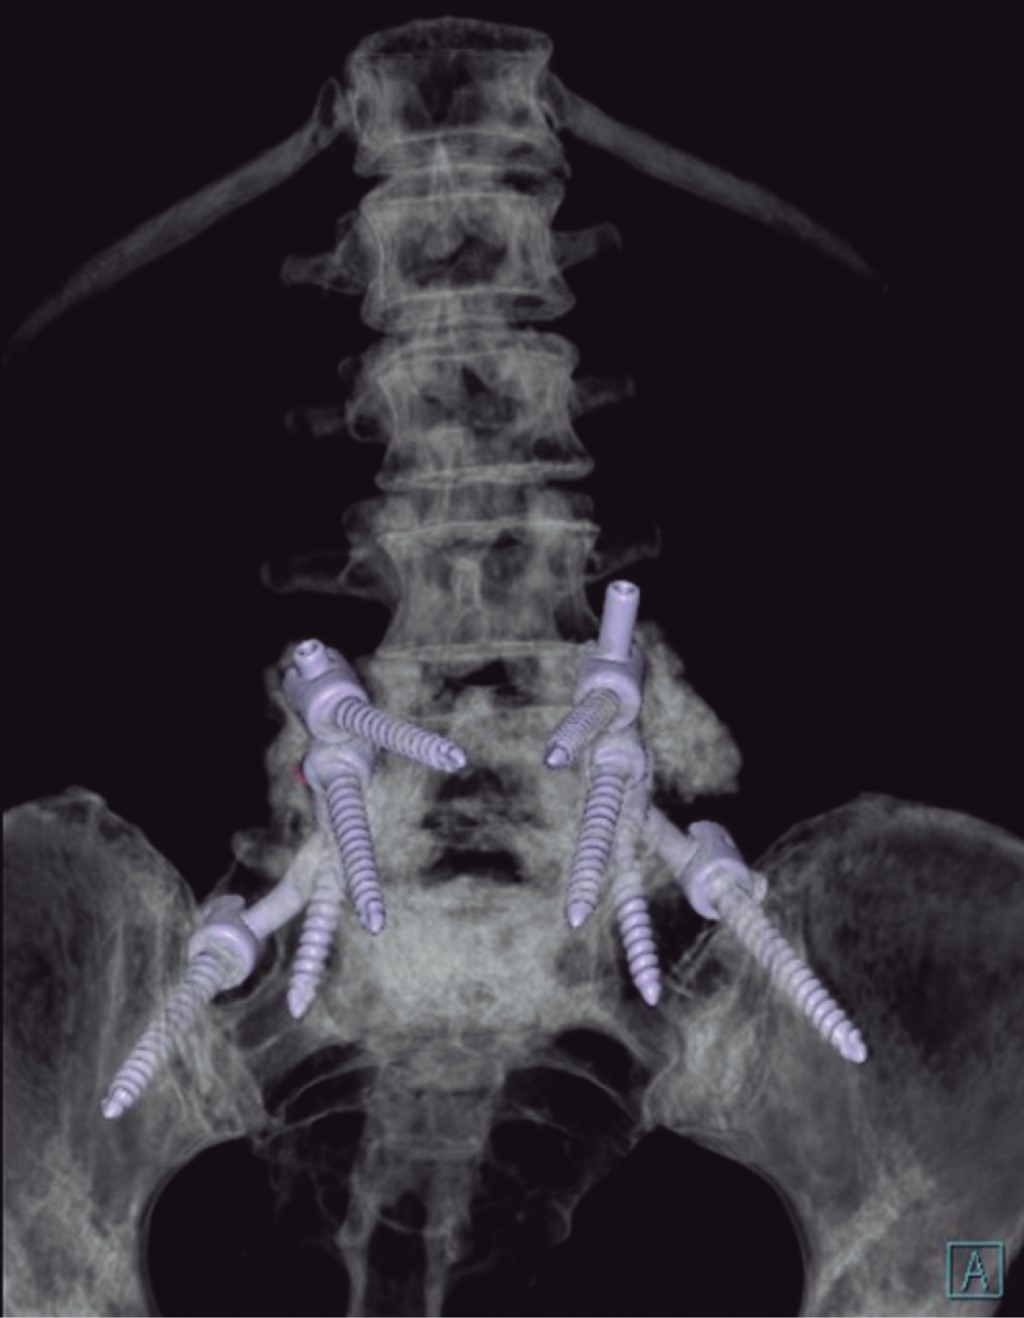

Ozone is a medical gas described since the 19th century; the ozone therapy has evolved to date in terms of its applications and its usefulness in various diseases due to its action at the molecular level and in dissimilar diseases associated with painful processes of inflammatory origin such as present in herniated discs of the spine, although the benefits of its application are currently in controversy, as well as the various complications that may occur after its application. Pneumocephalus is a complication that occurs in the background of a head injury or neurosurgery. Ozone infiltrations are used for the treatment of disc prolapse to reduce clinical symptoms. The anti-inflammatory effect of ozone is supported by its ability to oxidize compounds that contain double bonds such as arachidonic acid and prostaglandins, which are active substances with high concentrations in the inflammatory process. The appearance of pneumoencephalus and arachnoiditis chemical after epidural injection and also with ozone infiltrations is a rare complication but it has been described in recent years as a devastating post-application complication. Arachnoiditis can present as sensory and motor deficits, paresthesias, transient radicular neurological syndrome (TRNS), cauda equina syndrome, and conus medullaris. In relation to arachnoiditis, cases as severe as cauda equina syndrome after spinal anaesthesia, and more benign such as TSNR have been described, characterized by low back pain that radiates to the lower extremities, and not associated with motor deficits. neither sensitive, nor sphincter incontinence, which appears in the first 24 hours, which can last several days, and which resolves without neurological sequelae. Understanding the pathophysiology is important to assess and diagnose this type of neurological complications, especially in patients with disc disease who have undergone this type of treatment. The purpose of this report is to present the case of a patient with disc disease with the presence of radiculopathy who underwent infiltration by ozone therapy, who immediately presented complications such as pneumoencephalus and chemical arachnoiditis that led her to remain hospitalized in intensive care and present cauda equina syndrome.REFERENCES